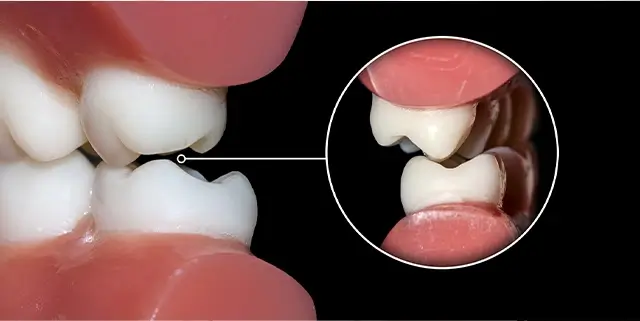

入れ歯とは違う、自分の歯のような感覚

Before

After

歯を失った箇所に人工の歯根(インプラント)を埋入し、歯を補う治療法です。入れ歯やブリッジなどと比較すると健康的なデメリットが少なく理想的な治療といえます。

| 治療期間 | 5ヶ月 |

|---|---|

| 治療費 | ¥1200,000+税 |

| 治療のリスク | インプラントが歯周病になる可能性がある |